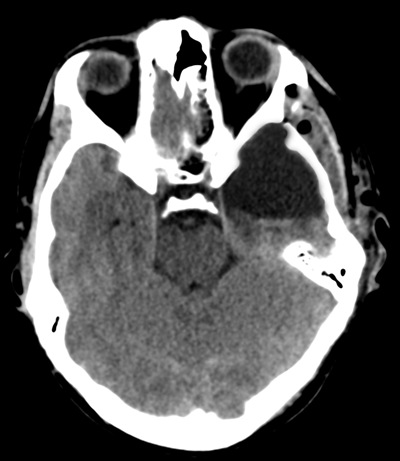

Intervenția chirurgicală a fost un adevărat succes! Operația a durat 6 ore, dintre care 4 ore pacientul s-a aflat în contact verbal deplin cu echipa operatorie. În timpul operației pacientul a putut să vorbească, să citească versuri, să calculeze în mai multe limbi, îndeplinea cu mâinile diferite instrucțiuni motorii. A fost transferat în salon a doua zi, iar externat – peste 6 zile după operație. Examenul de control computer-tomografic a arătat lipsa complicațiilor și rezecția totală a tumorii, care s-a dovedit a fi un proces cu malignitate joasă. Defecte neurologice postoperatorii nu s-au constatat.